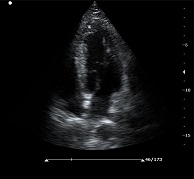

C7便攜式彩超產(chǎn)品說(shuō)明:

? ? ? ?C7為深圳安盛生物醫(yī)療技術(shù)有限公司新一代便攜式彩超產(chǎn)品,采用了先進(jìn)的PC平臺(tái),擁有強(qiáng)大的處理能力,優(yōu)異的圖像性能,集小巧輕便、全面的功能與輕巧流暢、特有的U型設(shè)計(jì)與一身,提供大眾新選擇。

先進(jìn)的成像技術(shù):

? ?● PHI脈沖反相組織諧波成像+頻率復(fù)合技術(shù)

? ? ? ?保證良好穿透力的同時(shí)獲得更加細(xì)膩的二維圖像

? ?● 空間復(fù)合成像技術(shù)

? ? ? ?通過(guò)多個(gè)角度圖像復(fù)合減弱單一圖像偽像,提高信噪比

? ?● 斑點(diǎn)噪聲抑制技術(shù)

? ? ? ?消除二維圖像斑點(diǎn)噪聲,顯著提高圖像信噪比

? ?● 多種成像模式

? ? ? ?B、C、PW、CW、BCD三功、大角度偏轉(zhuǎn)成像、實(shí)時(shí)寬景成像、梯形成像(僅支持線陣)、解剖M型、彩色M型成像、組織多普勒成像、3D/4D成像